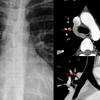

Pericardial stripe